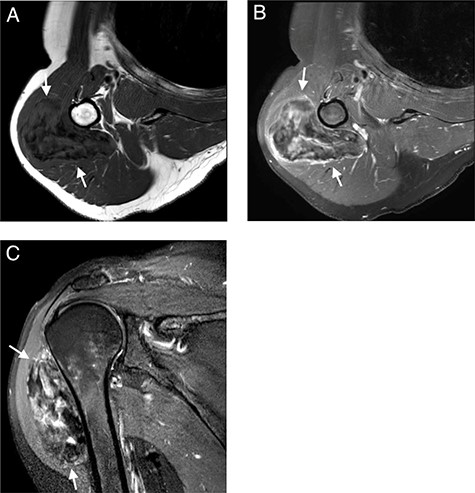

MRI with (A); axial T1-WI; (B) axial T1-FS-WI after administration of intravenous gadolinium contrast and (C) sagittal T2-FS-WI. Heterogeneous tumoral mass indicated with long arrows.

Subsequent MRI showed a well-circumscribed ovoid mass beneath the deltoid muscle abutting the humeral bone without evidence of invasion of the bone or the adjacent neurovascular structures. The mass was heterogeneous isointense to muscle on T1 and heterogeneous hyper- and isointense to muscle on T2-fat-saturated images, embedded were multiple T1 and T2-fat-saturated hypointense foci, suggesting the possibility of internal calcifications or fibrous strands (Fig. 2A and C). The mass showed limited peripheral enhancement and septae, with a slow initial phase and plateau on dynamic contrast-enhanced images (Fig. 2B). No diffusion restriction was noted.

MRI shows variable signaling depending on the sequence. Desmoplastic fibroblastoma shows weak to intermediate T1 signaling and a high T2 weighted signaling [5, 14, 15]. T1-weighted imaging shows a heterogenous consistency and signal intensity comparable to skeletal musculature [13]. The fat-suppressed imaging shows greater heterogeneity than the T1-weighted imaging, with a weaker signaling. Yamamoto et al. described a specific T1-weighted fat-suppressed peripheral rim post-contrast administration. They assume a difference in vascularization between the inner and utmost outer layer of the tumor [5]. With fat suppression, pathological processes tend to delineate vividly.